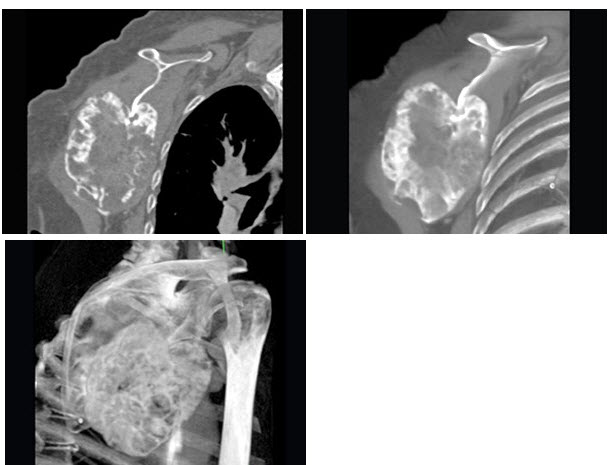

27、单项选择题

根据所提供图像,最可能的诊断是()

男,33岁,右肩部疼痛,巨大肿块,活动受限,结合图像,最可能的诊断是()

A.骨肉瘤

B.软骨瘤

C.骨软骨瘤

D.软骨肉瘤

E.骨转移瘤